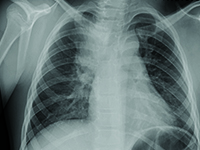

InneWady wrodzone to nieprawidłowości budowy narządów powstałe przed urodzeniem, które prowadzą do zaburzeń czynności tych organów. Szacuje się, że na powstawanie wad wrodzonych mają wpływ: czynniki toksyczno-środowiskowe (w 5-10%) i genetyczne (w 20-25%), ale w 70-80% nie udaje się ustalić żadnej przyczyny. Częstość występowania wszystkich wad wrodzonych u noworodków i niemowląt wynosi około 4%, poniżej 4% z nich (około 3,9%) dotyczy układu oddechowego. Prawie połowa dzieci z wadami wrodzonymi układu oddechowego umiera przed ukończeniem piątego roku życia. Do objawów wad układu oddechowego należą przewlekanie lub nawracanie infekcji dróg oddechowych, objawy niewydolności oddechowej, kaszel, krwioplucie. Niekiedy wada układu oddechowego jest bezobjawowa i wykrywana przypadkowo.